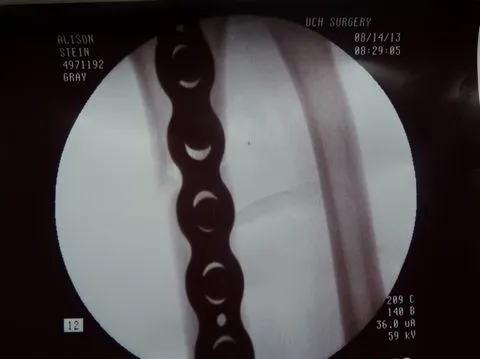

Dr. Gray used flouroscopy to confirm that the fracture margins were in perfect alignment, secured by three screws proximal and three screws distal to the fracture.

In fact, one view (below right) shows such tight apposition and such perfect alignment, that one cannot even see the fracture margins.